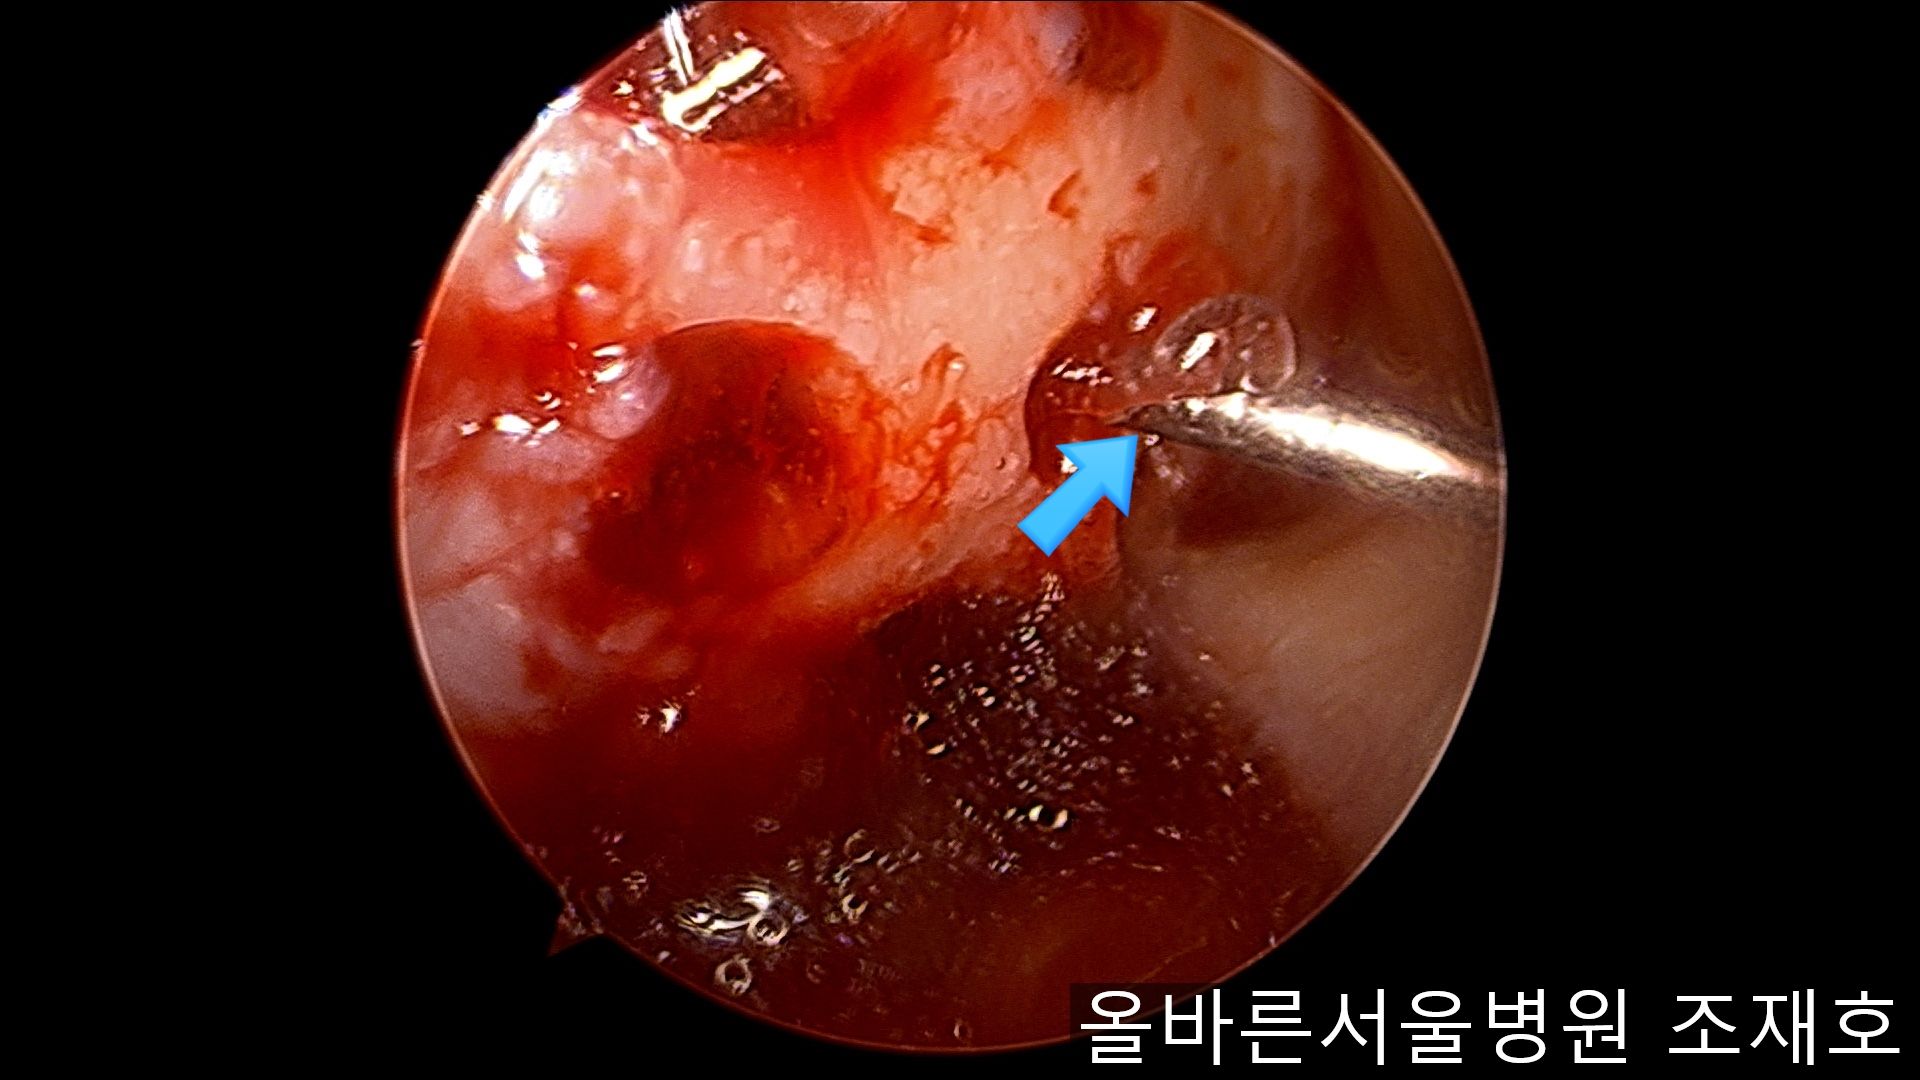

在股骨部位用CARTISTEM注射用4mm激光钻细密打孔,并确保软骨板不倒塌。不用切开通过关节镜即可完成手术。

如图,尽量细密打孔。

用水冲洗清理空间,为注入CARTISTEM做准备。

以注射的方式将CARTISTEM填满每一个孔。

填充完每个孔后将剩余的CARTISTEM涂抹在孔上方。